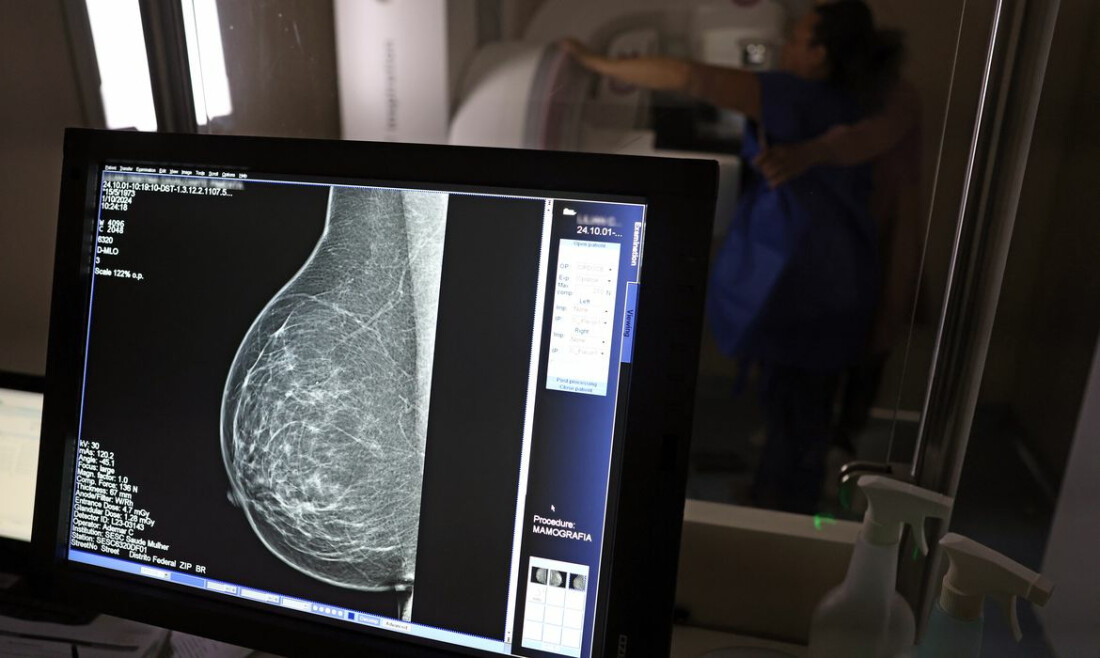

A partir de quantos anos se deve fazer a mamografia de rastreio, ou seja, como um exame de rotina, mesmo sem sintomas? Para autoridades públicas, como o Ministério da Saúde e o Instituto Nacional do Câncer (Inca), o ideal é que a mamografia seja feita a cada dois anos por todas as mulheres entre 50 e 69 anos. Algumas entidades médicas, como a Sociedade Brasileira de Mastologia (SBM), entretanto, recomendam exame anual a partir dos 40 anos. As divergências ganharam notoriedade há alguns dias, depois que a Agência Nacional de Saúde Suplementar (ANS) fez consulta pública sobre as atualizações do Manual de Boas Práticas em Atenção Oncológica, usado no Programa de Certificação de Boas Práticas em Atenção à Saúde. Órgão regulador dos planos de saúde, cabe à ANS fiscalizar o serviço prestado e criar normas e outras iniciativas que melhorem o atendimento à população.  Entre os critérios para que as operadoras de planos de saúde sejam certificadas, está a realização de exames de rastreamento de diversos tipos de câncer, o que contribui para o diagnóstico precoce. No caso do câncer de mama, a minuta elaborada pela ANS estabelece o rastreamento organizado, com a convocação de todas as beneficiárias dentro da faixa etária para fazer a mamografia e outros exames complementares que forem necessários. Até esse ponto, há consenso. "A melhor maneira de desenvolver a linha de cuidados do câncer é tentar fazer o diagnóstico da doença o mais precocemente possível. Porque quanto mais precoce for o diagnóstico, o tratamento é mais efetivo e é menos dispendioso", diz o diretor-geral do Inca, Roberto Gil.  A mastologista Rosemar Rahal, que integra a Sociedade Brasileira de Mastologia (SBM) e a Federação Brasileira das Associações de Ginecologia e Obstetrícia (Febrasgo), complementa: "Este é o caminho, não tenho dúvida. Os países que reduziram a mortalidade por causa de câncer de mama conseguiram fazendo o rastreamento organizado."  Divergências A ANS decidiu, entretanto, seguir em sua minuta o protocolo do Inca, que também é adotado no Sistema Único de Saúde (SUS) e preconiza a realização de mamografia de rastreio apenas a partir dos 50 anos, com intervalo de dois anos entre os exames, caso nenhum problema seja encontrado. "O rastreamento do câncer deve ser direcionado às mulheres na faixa etária e periodicidade em que há evidência conclusiva sobre redução da mortalidade por câncer de mama e em que o balanço entre benefícios e possíveis danos à saúde dessa prática seja mais favorável", diz a minuta.  A escolha motivou protestos de várias entidades médicas, que defendem a inclusão de pessoas de 40 a 50 anos e a realização anual dos exames. "Esse já é um posicionamento das sociedades médicas há alguns anos. Nós já temos três diretivas publicadas pela SBM, pela Febrasgo [Federação Brasileira das Associações de Ginecologia e Obstetrícia] e pelo Colégio Brasileiro de Radiologia nos anos de 2012, 2017 e 2023, colocando o que essas três sociedades médicas consideram como sendo ideal para o rastreamento mamográfico no Brasil. (...) Porque nós temos no Brasil 25% dos cânceres de mama entre 40 e 50 anos de idade. Então, se nós fazemos esse rastreamento só a partir dos 50 anos, estaremos postergando o diagnóstico. Essa lesão prolifera dentro desse tecido mamário e chega para gente em um estágio mais avançado", afirma Rosemar Rahal. O diretor-geral do Inca enfatiza que o protocolo do instituto está de acordo com a recomendação da Organização Mundial da Saúde (OMS) e da Agência Internacional de Pesquisa em Câncer: "A informação científica que temos hoje não é da opinião de um especialista, é da literatura médica, avaliada com o nível de evidência 1, meta-análise e estudo randomizado, que é o maior nível de evidência que se tem. Grande parte dos trabalhos não conseguiu mostrar nenhum aumento de sobrevida na faixa dos 40 aos 50 anos. Só houve aumento de sobrevida na faixa de 50 a 69 anos." Roberto Gil explica por que esses estudos consideram que os 50 anos são a idade certa para o início do rastreamento na população em geral: "Não estamos negando que mulheres abaixo de 50 anos tenham câncer de mama. Estamos falando que, abaixo dos 50 anos, acumulam-se outros problemas e o rastreamento populacional é menos eficiente. A mamografia é um exame de raio X, que vai ser mais efetivo na medida que a mama seja menos densa e que se tenha mais contraste na imagem, para não se confundir o parênquima normal com um nódulo. Então [antes dessa idade], aumenta muito mais a possibilidade de ter falsos positivos e ter que fazer mais exames. Posso fazer uma biópsia e ser mais difícil interpretar e levar a uma cirurgia desnecessária."  O médico afirma também que a mudança da faixa etária pode atrapalhar o rastreamento da população atualmente incluída. "Hoje, 30% das mulheres brasileiras nunca fizeram uma mamografia. Então, para dar um exemplo, seria como se eu estivesse fazendo um salto em altura. Eu botei o meu sarrafo em 2 metros e não estou conseguindo pular. A minha próxima medida vai ser tentar melhorar e treinar muito para pular os 2 metros, ou elevar o sarrafo para 2,50?"  A mastologista Rosemar Rahal, porém, ressalta que o aumento da demanda não seria um problema por si só. "No Brasil, não temos déficit de aparelho de mamografia, temos déficit de mamografias. O aparelho está lá, mas não é usado. E aí tem uma série de questões que vêm à tona. Talvez esse exame não seja solicitado, ou quando é solicitado a paciente não faz por medo do exame e do diagnóstico. A nossa questão não é de falta de equipamento, a nossa questão é de comunicação." Cobertura Quando a discussão chegou às redes sociais, muitos usuários começaram a dizer que a ANS pretendia mudar as regras de cobertura, impedindo mulheres mais jovens de fazer a mamografia pelos planos A agência esclareceu que os critérios do manual se referem apenas ao programa de certificação, que é de adesão voluntária das operadoras, e não tem nenhuma relação com o chamado rol obrigatório: uma lista com todas as consultas, exames, cirurgias e tratamentos que as operadoras devem cobrir.  Atualmente, o rol garante direito à mamografia bilateral para mulheres de qualquer idade, conforme indicação médica, e mamografia digital, dos 40 aos 69 anos. Até a Secretaria de Comunicação Social da Presidência da República divulgou nota enfatizando que os planos de saúde não podem negar mamografia, sob pena de multa.  Mesmo assim, a mastologista Rosemar Rahal teme que a adoção do manual com a redação atual possa embasar negativas de cobertura por parte dos planos de saúde: "Se a Agência Nacional coloca um selo de qualidade e considera como qualidade realizar mamografia a partir dos 50 anos, de 2 em 2 anos, toda a saúde suplementar vai considerar aquilo como ideal. O que a gente acredita é que, se o documento for publicado desse jeito, os planos de saúde vão assumir isso como regra." Na última segunda-feira (27), a ANS realizou reunião com representantes de diversas entidades médicas para esclarecer dúvidas sobre a consulta pública e concedeu prazo de 30 dias para que s apresentem os estudos científicos e dados técnicos que embasam o pedido de mudanças nos critérios de rastreamento. Além disso, a ANS recebeu mais de 63 mil contribuições por meio da consulta pública e informou que vai analisar todas as propostas recebidas.  Relacionadas Saúde incorpora cinco procedimentos contra câncer de mama no SUS Estudo em larga escala aplica IA para detectar câncer de mama Médicos reafirmam eficácia da mamografia para prevenir câncer de mama